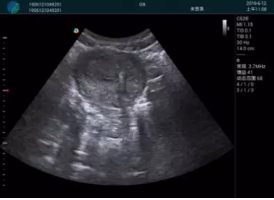

清晰顯示孕囊,通過(guò)軟件包計(jì)算孕齡7w+6d

M20實(shí)時(shí)引導(dǎo),術(shù)中清晰顯示孕囊被破壞和抽吸針的過(guò)程,清晰顯示吸引針

抽吸結(jié)束后縱切子宮,孕囊已被完全抽吸,未見(jiàn)明顯殘留

橫切子宮,發(fā)現(xiàn)右側(cè)宮腔靠近宮角處有少許脫模樣殘留

M20引導(dǎo)下,抽吸針找到右側(cè)宮角處再次清掃

二次抽吸后再次進(jìn)行超聲檢查,宮腔未見(jiàn)殘留,宮腔線(xiàn)清晰顯示